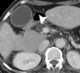

Papillary necrosis with sloughed papilla

Renal papillary necrosis is a form of nephropathy involving the necrosis of the renal papilla. Lesions that characterize renal papillary necrosis come from an impairment of the blood supply and from subsequent ischemic necrosis that is diffuse. [Source: Wikipedia ]